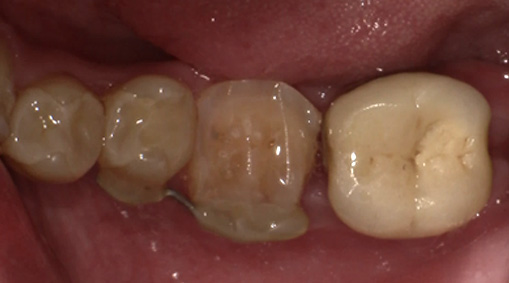

6日目(術後3-4週目) 歯内治療を開始します。

術後4週目の移植した歯牙。固定は維持されている。

ラバーダム(ゴム製の布)を装着し、歯の中の治療をします。 -

7日目(術後3-4週目) 歯内治療の続きをします。

仮蓋を除去します。

歯の中にお薬を入れます。

8日目 支台築造し、型どりをします。

最終の材料を入れて歯の土台を形づくります。